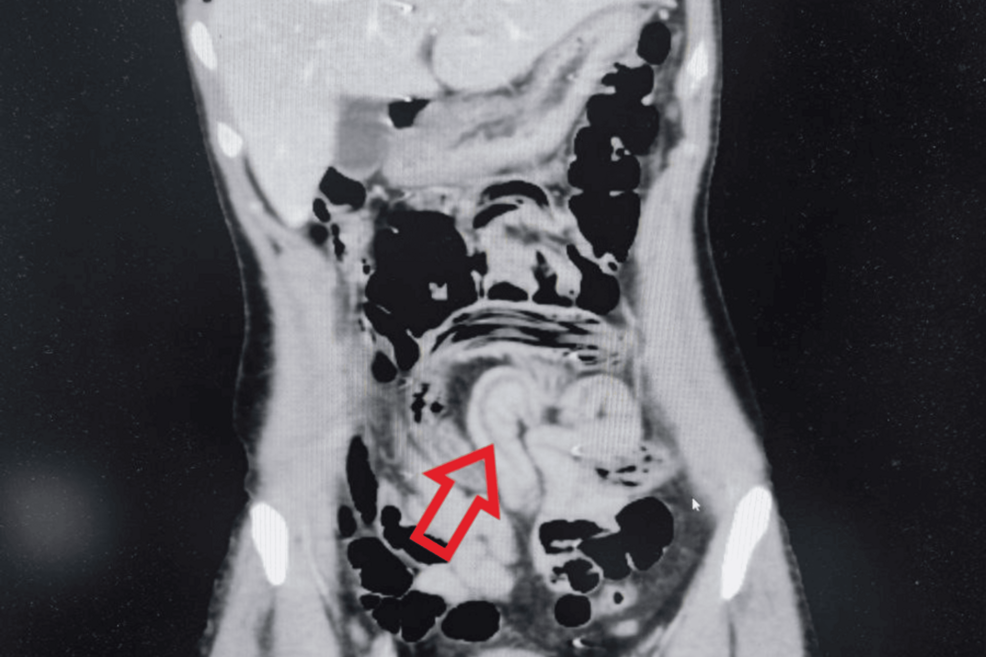

정맥 조영제를 이용한 복부 컴퓨터 단층촬영으로 소장과 대장 고리에서 공기로 채워진 선형적 공동 변화가 관찰됐다. 큐레우스

의료진은 컴퓨터단층촬영(CT)을 통해 장내에 존재하는 가늘고 긴 이물질을 포착해 회충 감염을 의심했다.